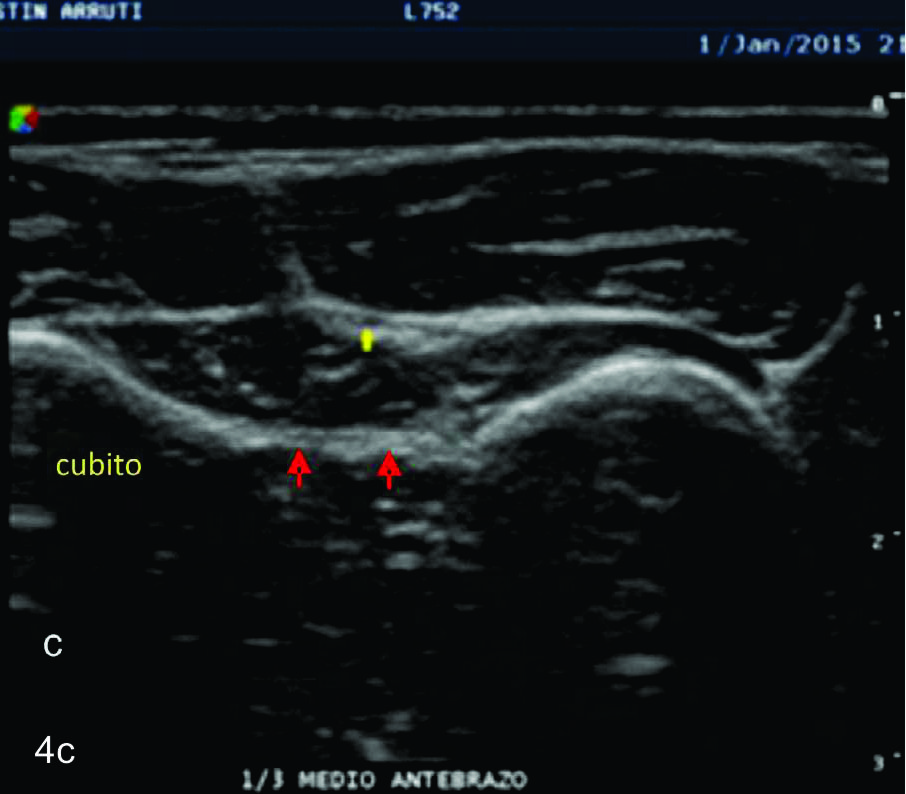

Figura 4

Nervio interóseo posterior

Serie de cortes axiales del nervio interóseo posterior, desde su origen a nivel del codo como rama terminal del nervio cubital hasta su terminación en la cara posterior del antebrazo. Se identifica el mismo señalado por flechas amarillas, supinador- Músculo supinador, flechas azules- ambas cabezas del supinador, flechas rojas- membrana interósea. A- tercio proximal antebrazo previo al ingreso al canal supinador, B- tercio proximal del antebrazo en el canal supinador entre los dos haces del supinador, C- tercio medio del antebrazo, localizado entre el plano muscular